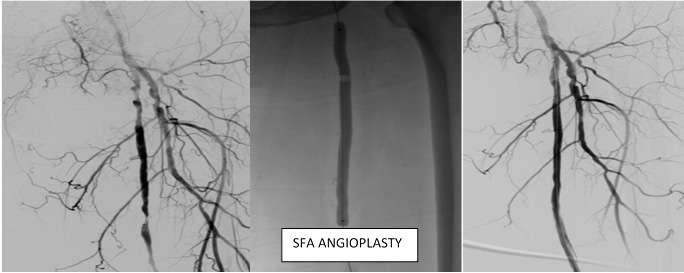

ANGIOPLASTY

Angioplasty uses inflatable devices called balloons to open up narrowed arteries. Various types of balloons are used in different situations, including balloons that stretch arteries open, metal-edged balloons that cut and break up calcium deposits, and drug-coated balloons that can prevent scarring and future narrowing of the artery. During angioplasty, the interventional radiologist guides a catheter with a tiny balloon tip through the blood vessels into the blockage. The balloon is inflated to widen the artery, which restores blood flow.